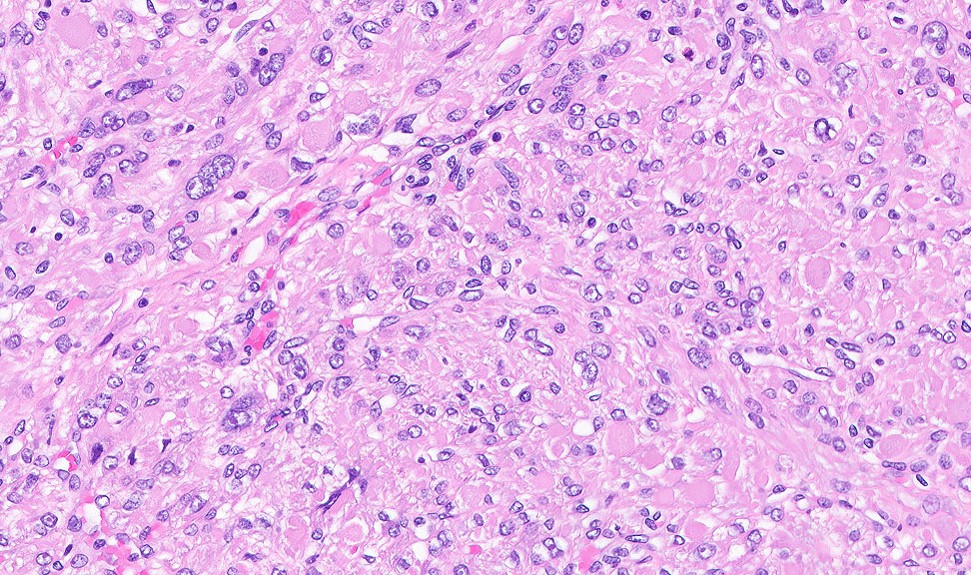

Microscopic (histologic) description

- Leiomyoma with bizarre nuclei:

- Bizarrely shaped, hyperchromatic, multilobulated nuclei with nuclear pseudoinclusions

- Arranged in a multifocal to diffuse distribution in a background of a typical leiomyoma (Am J Surg Pathol 2014;38:1330, Mod Pathol 2017;30:1476, Am J Surg Pathol 2016;40:923, Cancer 2014;120:3165, Am J Surg Pathol 1997;21:1261)

- Alveolar edema, staghorn vessels

- Low mitotic activity (< 5 mitoses/10 high power fields)

- Absence of tumor cell necrosis

- Vasculature variable (staghorn vessels, thick walled vessels, fibrinoid necrosis of vessel walls, luminal vascular obliteration)

- Diagnostic key: intermixed normal spindled smooth muscle cells

Contributed by Sabrina Croce, M.D., Ph.D., Kristina Doytcheva, M.D., Jennifer A. Bennett, M.D. (Case #508) and @Andrew_Fltv on Twitter